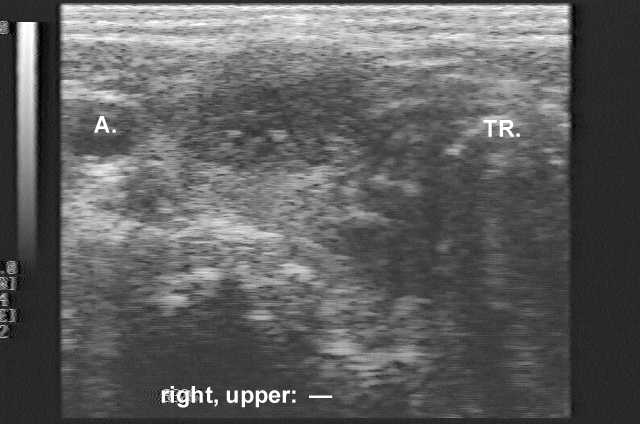

Ultrasonography. The thyroid was intact except for a hypoechogenic inhomogeneous nodule in the right thyroid.